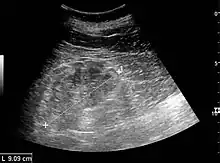

Ultrasound

Kidney ultrasonography is useful for diagnostic and prognostic purposes in chronic kidney disease. Whether the underlying pathologic change is glomerular sclerosis, tubular atrophy, interstitial fibrosis, or inflammation, the result is often increased echogenicity of the cortex. The echogenicity of the kidney should be related to the echogenicity of either the liver or the spleen (Figure 22 and Figure 23). Moreover, decreased kidney size and cortical thinning are also often seen and especially when disease progresses (Figure 24 and Figure 25). However, kidney size correlates to height, and short persons tend to have small kidneys; thus, kidney size as the only parameter is not reliable.[54]